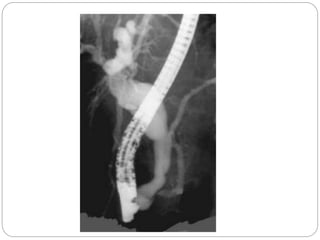

Fusiform choledochal cyst with a long common channel

and associated stricture at the pancreaticobiliary junction.

Fusiform choledochal cystwith a long common channel and associated stricture at the pancreaticobiliary junction.